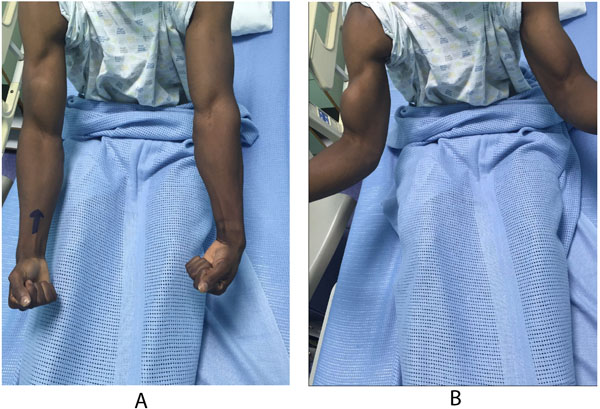

A 28 years old healthy man had a sudden jerk of his flexed right elbow to extension by the tension of the towrope as the boat accelerated away while involved in water skiing sports. He presented to the emergency department with severe pain in the anterior compartment of his right arm and a “Popeye” deformity, with clear rupture of the long head of the biceps (Figs. 1A, 1B). The plain radiographs of the left arm, elbow, and forearm did not reveal any fractures or dislocations. Magnetic resonance imaging showed complete proximal rupture of long head of biceps tendon.